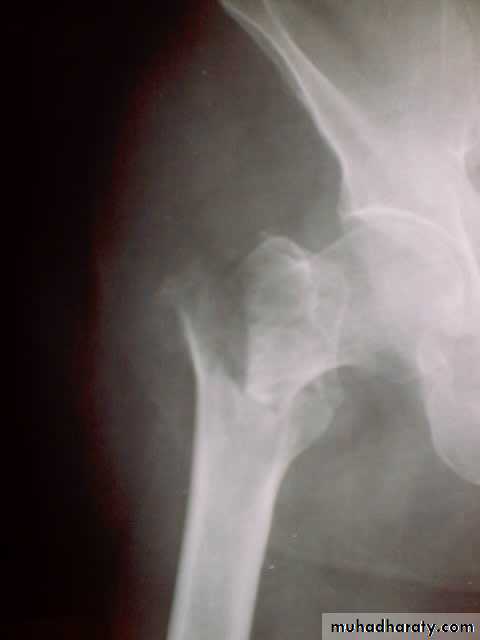

Pathological anatomy and classificationThe most useful is that of garden which is based on amount of displacement apparent in the pre-reduction x-ray of the neck femur.

Stage 1

impactedStage 2

complete fracture UndisplacedStage 3

complete with moderate displacement.Stage 4

severely displaced fracture.Fracture neck femur has poor capacity for healing

Radiological examination

two questions must be answered.Is there a fracture?

Is it displaced ?:Radiological classification

GRADE 1

:the femoral head is in its normal position or tilted into valgus and impacted on the femoral stump.GRADE 2

The femoral head is normally placed and the fracture line may be difficult to diagnosed

GRADE 3

The femoral head tilted out of position and the trabecular marking are not in line with those of innominate bone.GRADE 4

The femoral head trabeculae are normally aligned with those of innominate bone.